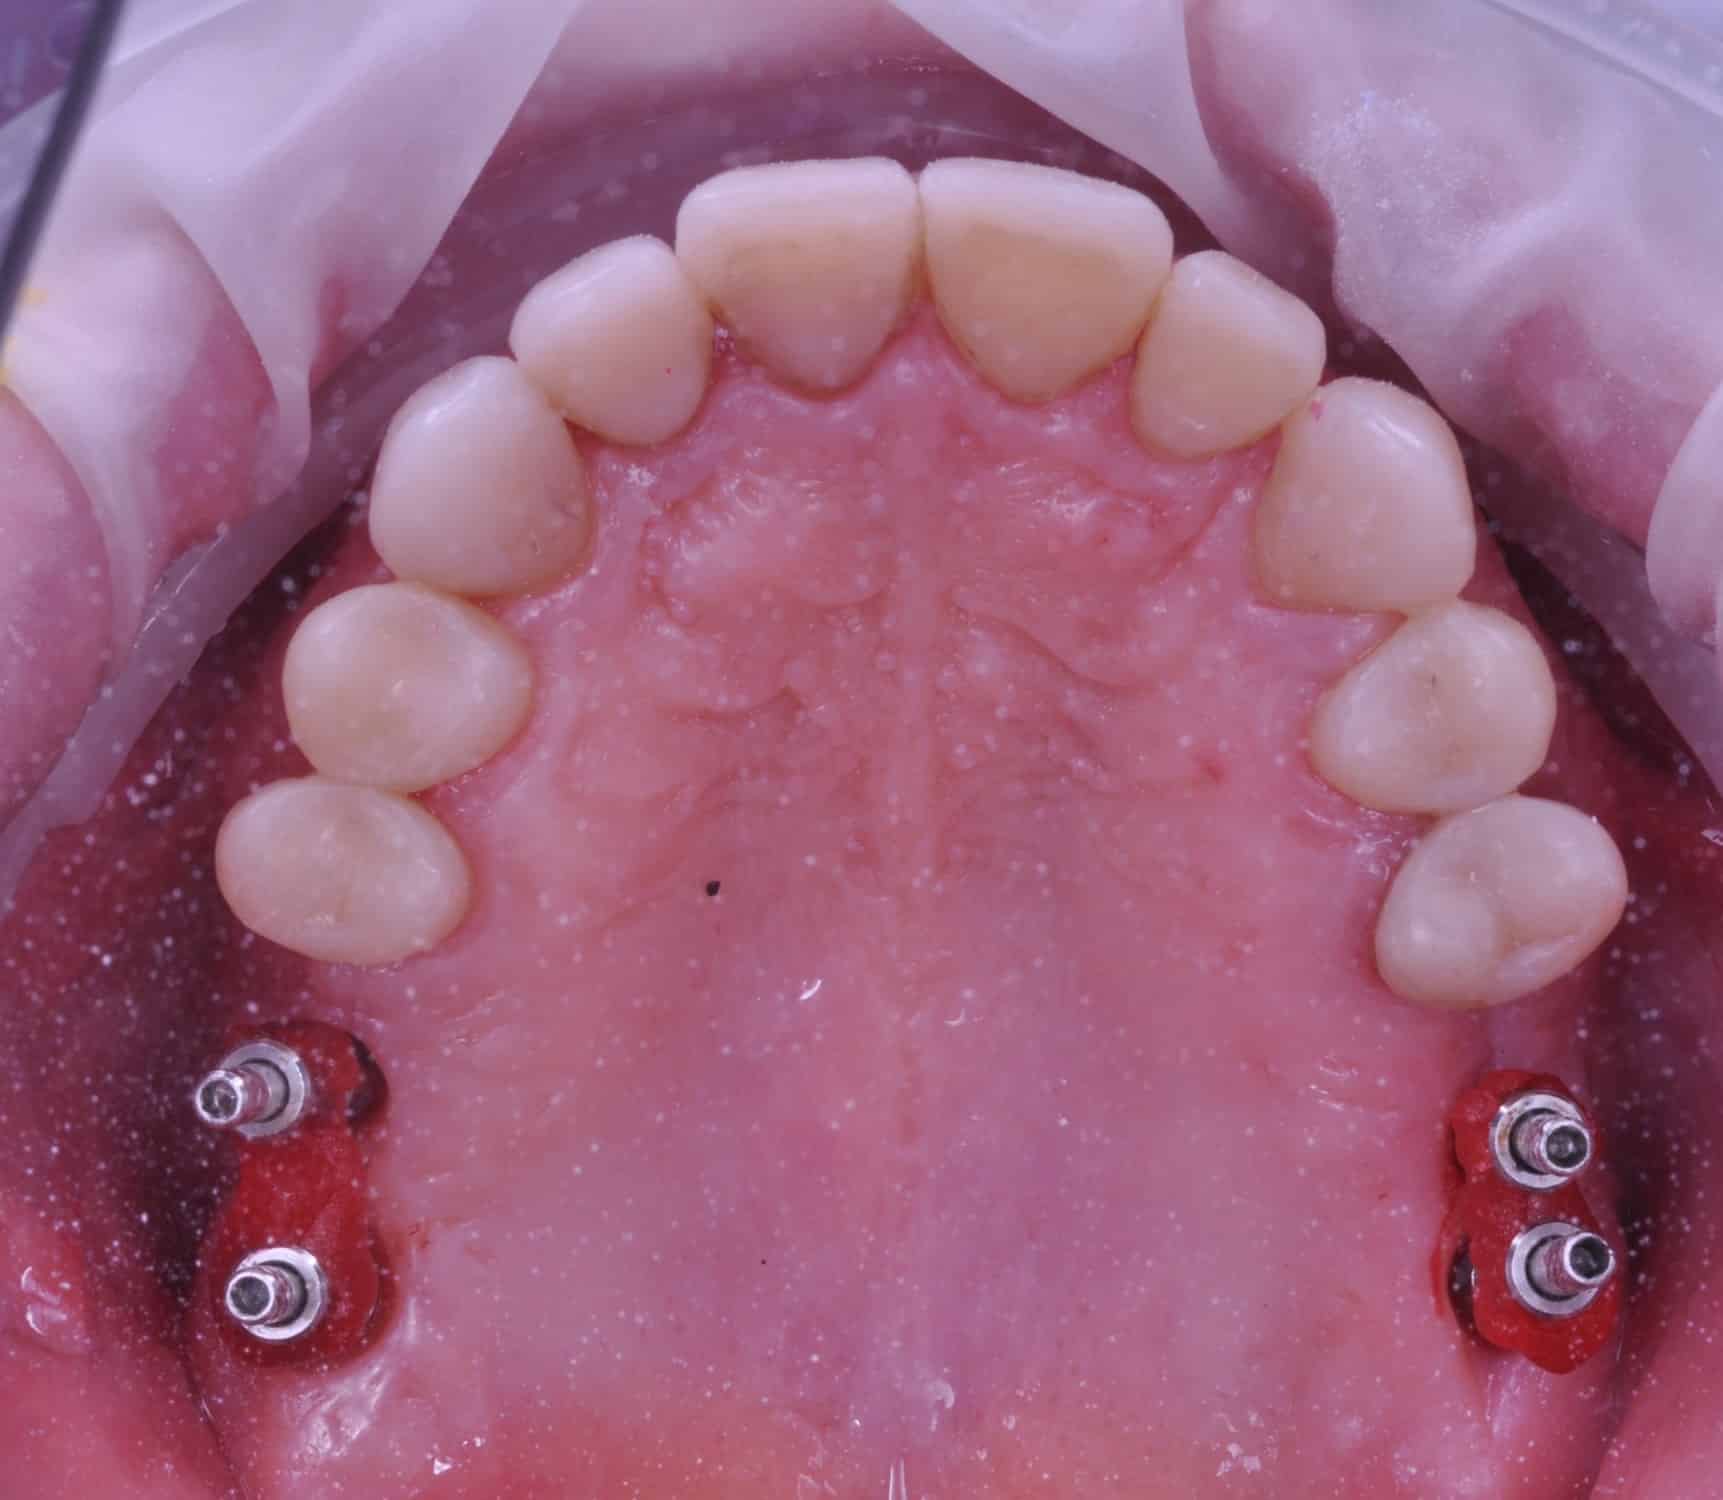

Împreună cu pacientul, am optat pentru inserarea implantelor cu ajutorul ghidului chirurgical pentru a plasa implantul în poziția protetică ideală și pentru a permite realizarea coroanelor insurubate pe implant. A fost efectuată scanarea digitală a arcadelor și a ocluziei pacientului, iar împreună cu tehnicianul radiolog de la DigiRay a fost suprapus fișierul .stl al amprentei digitale peste fișierul .dcm de la CBCT, utilizând software-ul 3Shape.

S-a planificat individual poziția și axul de inserție al fiecărui implant.

Doar astfel putem crea profilul de emergență corect al coroanei dentare, ceea ce permite conformarea papilei și a sulcusului.